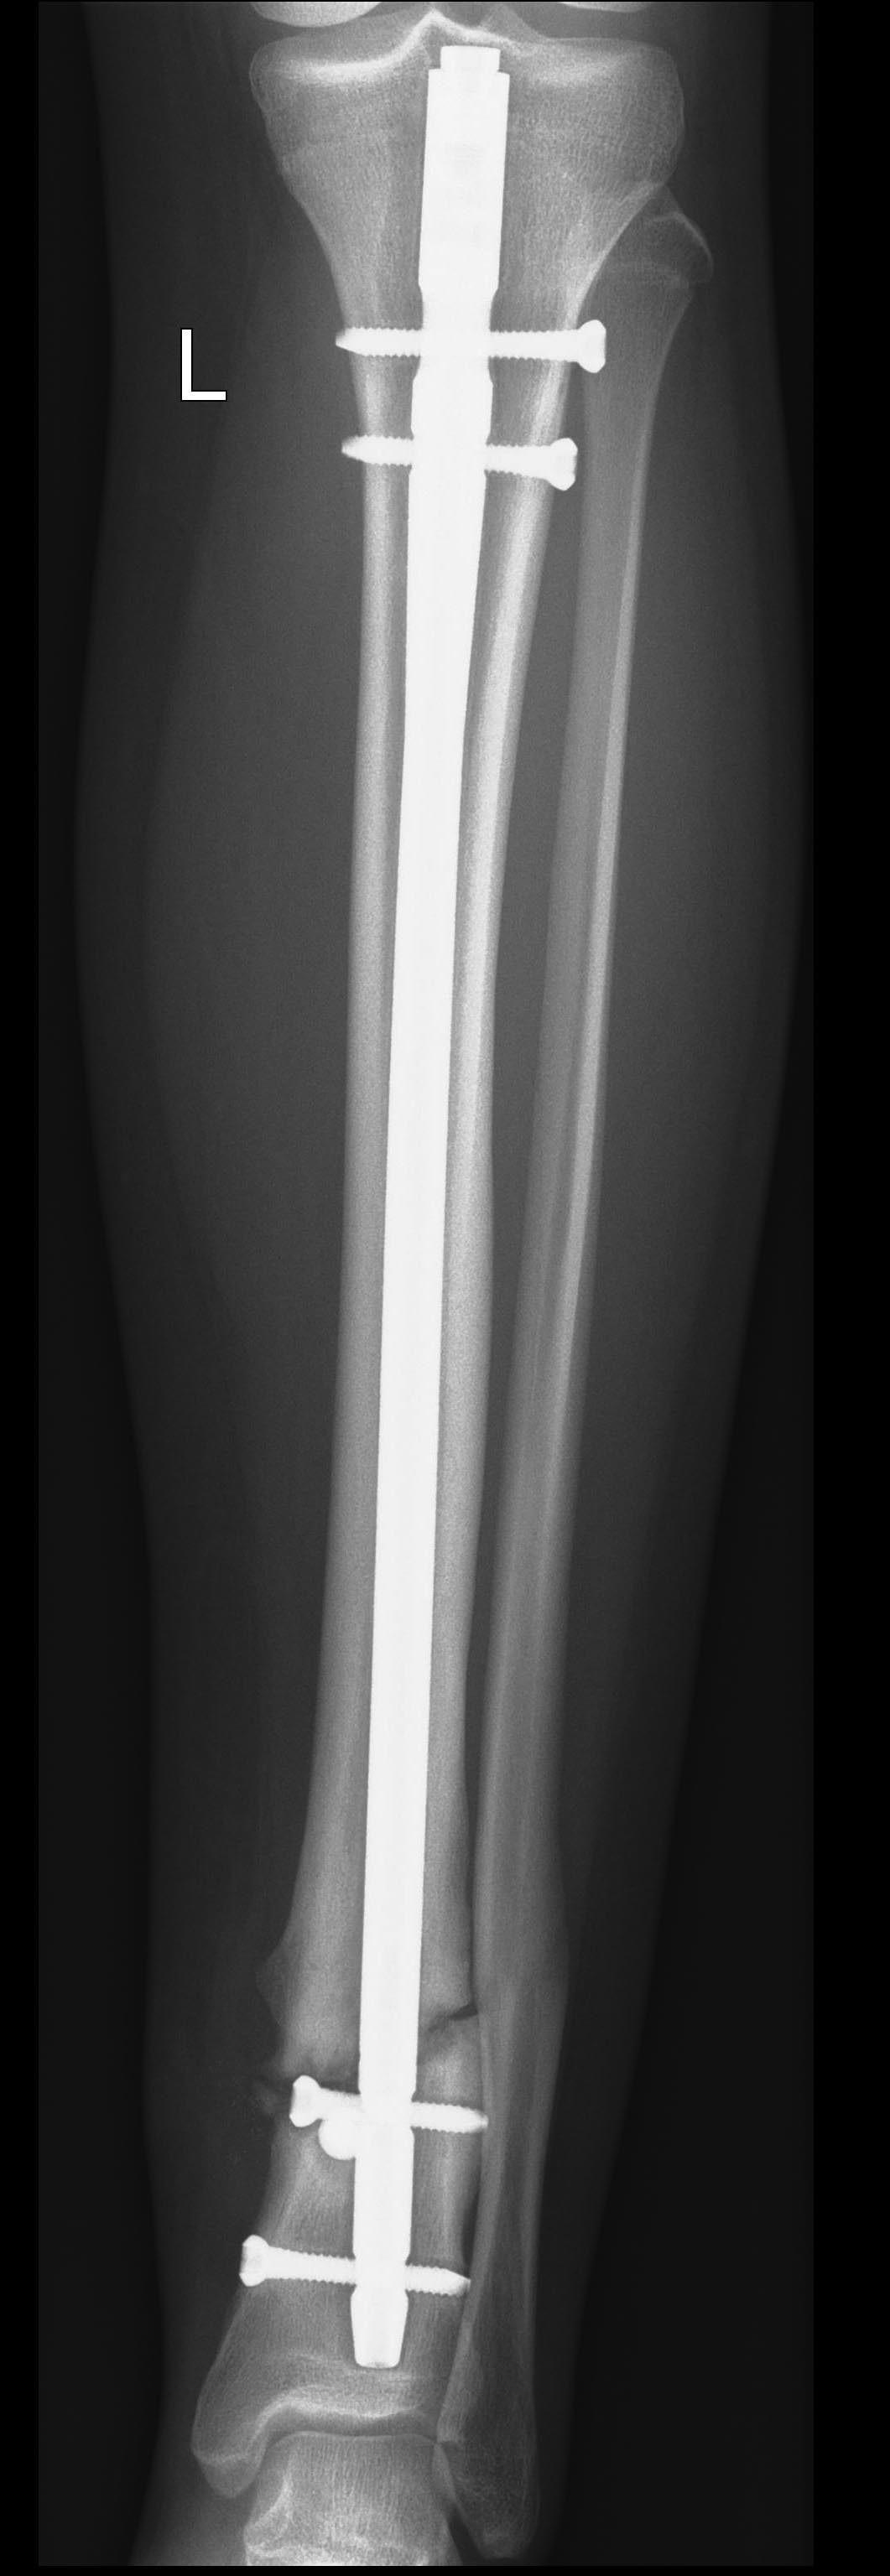

Добрый вечер уважаемые коллеги. На мой взгляд , причина несращения в нестабильности фиксации( проксимальный блокируемый винт в дистальном отделе штифта стоит прямо в переломе, так же как винт поллер. На контрольных снимках видна резорбция вокруг штифта и дистальных винтов. Вариант БИОС уже состоялся и закончить лечение предлагаю тем же. Считаю необходимым, учитывая срок после операции,R-картину нестабильности фиксации, выполнить удаление всей конструкции с ручным "нежным римированием" и установкой низкопрофильного штифта , места там хватит для 3-х винтов, без всяких поллеров. Малоберцовую лучше остеотомировать и проксимально заблокировать штифт сразу в динамике. Думаю сработает.

Полностью согласен с Андреем и в анализе причины и в предлагаемой ревизионной тактике. Один (самый дистальный) блокирующий винт и один poller\blocking screw явно недостаточны, а проксимальный из дистальных блокирующих винтов, проведенный через зону перелома, не работает, более того, вреден самим своим присутствием между отломками. Blocking screw(s) могут дополнять, но не заменять стандартные блокирующие винты, коих для этого перелома лучше бы 3.

Нестабильности тут не видно, т.е есть проблема не в ней.

Что видим? "Распорку" на фоне остаточного смещения периферического отломка кнаружи. Так что для улучшения условий для сращения надо устранить эту "распорку", т.е. сделать динамизацию.

Если эта мера уже запоздала, то сделать реостеосинтез с устранением и остаточного смещения, и без создания "распорки". Ну и рассверлить.

Не видно необходимости увеличивать стабильность фиксации дистального отломка больше той, что есть сейчас.